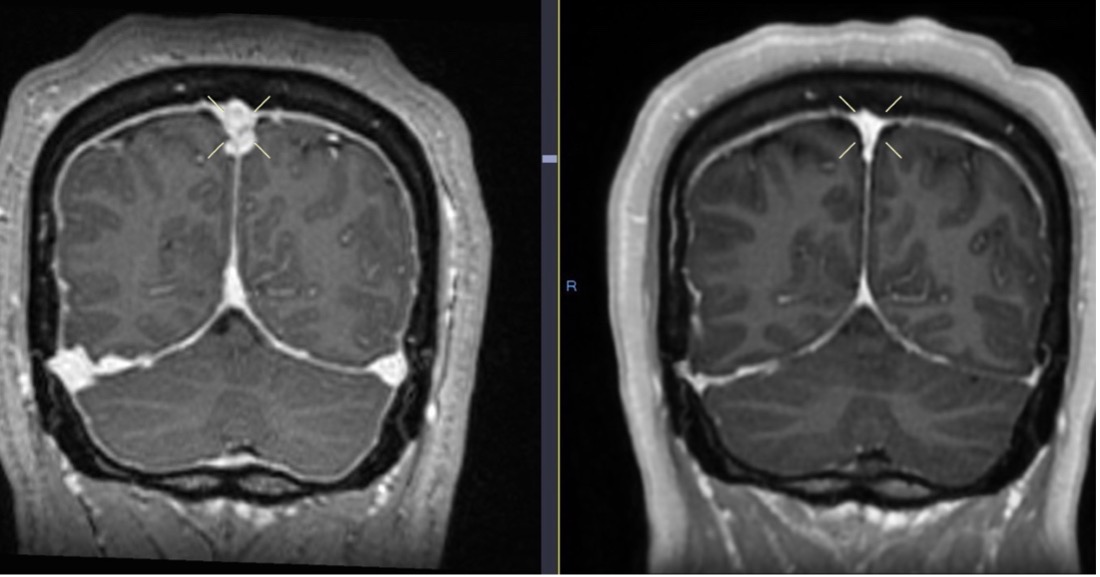

Outcome and follow-up. The plan was to continue anticoagulation and reassess clinically and with neuroimaging in 6 months. At her 6-month visit, she had no headache, a normal brain MRI, and no longer needed anticoagulation (Figures 9-11).

Fig. 9. Initial brain MRI (left) shows distention of the cerebral venous sinuses, with subsequent resolution 6 months later on follow-up MRI (right).

Fig. 10. Diffuse pachymeningeal thickening and enhancement on initial brain MRI (left), with interval resolution on follow-up MRI 6 months later (right).

Fig. 11. Initial brain MRI (left) shows enlargement of the pituitary gland, with resolution on follow-up MRI 6 months later (right).